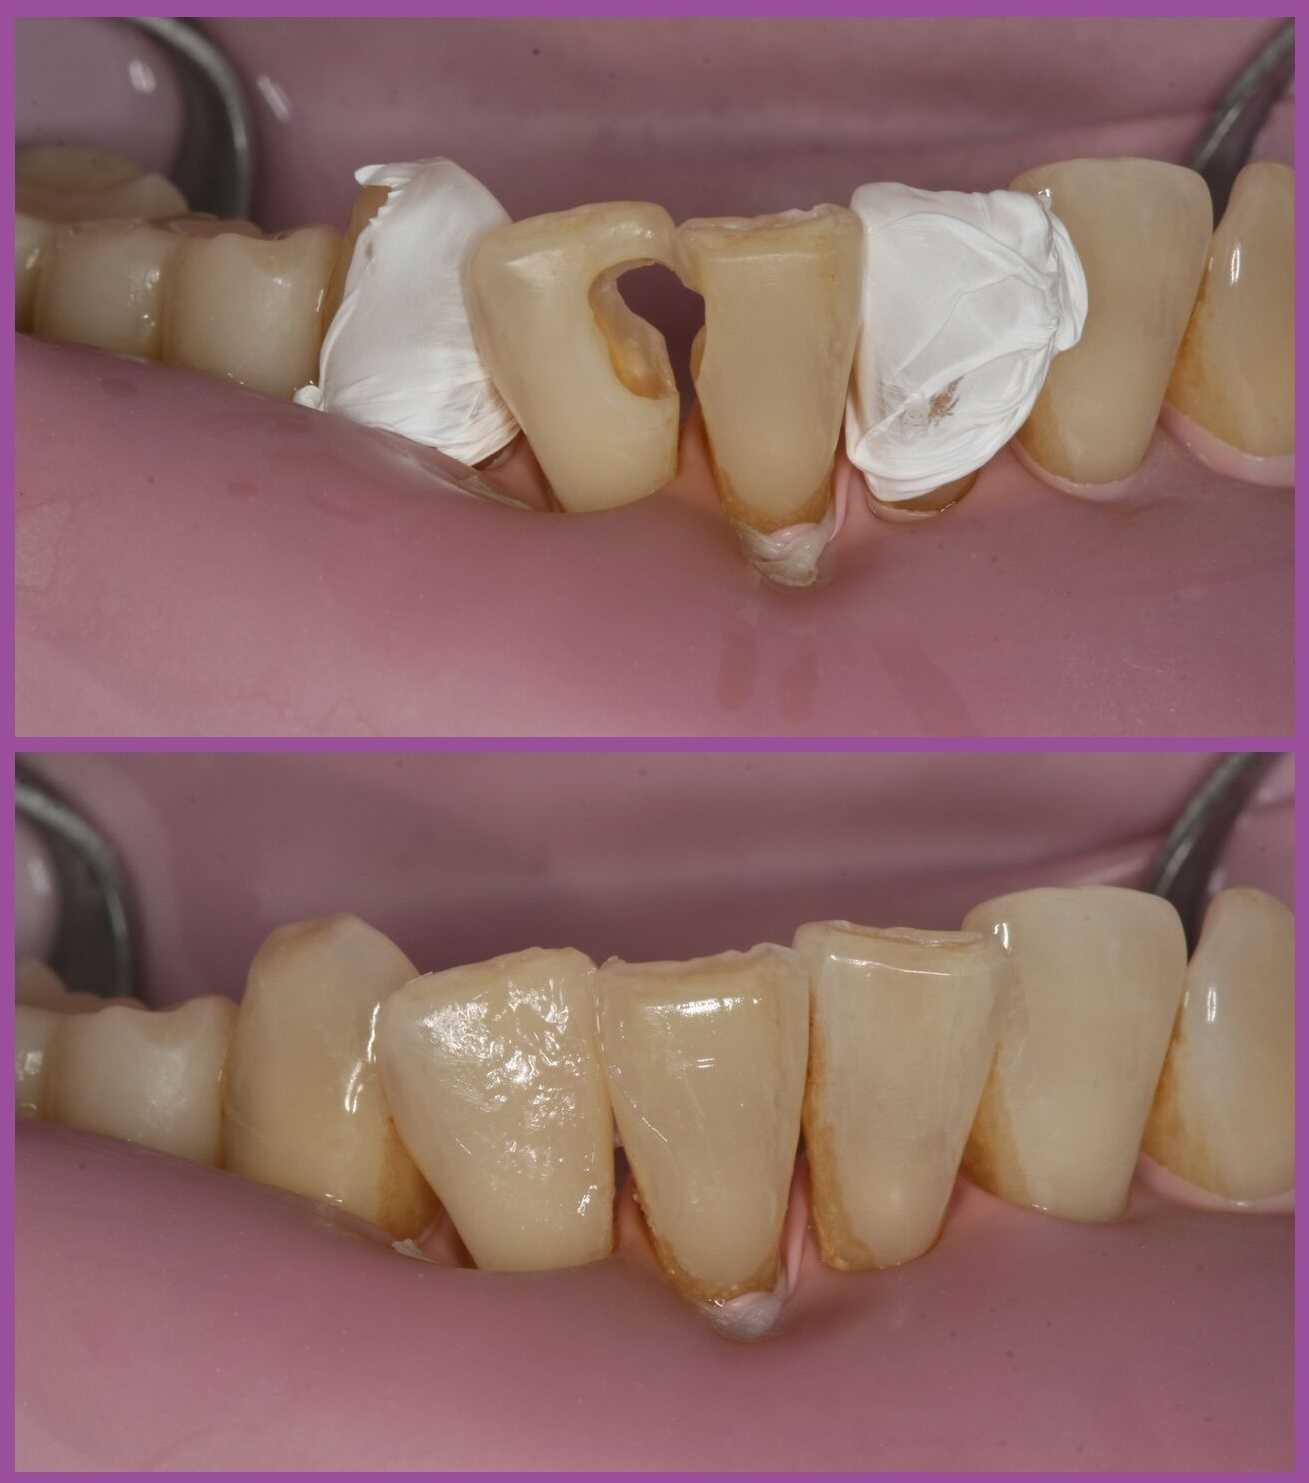

A mai modern fogászat fő célkitűzései a fájdalommentesség, a tartós végeredmény, a minimál invazív kezelések és végül, de nem utolsósorban az esztétikai szemlélet. Kis túlzással azt mondhatjuk, hogy 100 évvel ezelőtt még az volt a páciensek legfőbb kívánsága, hogy a kezelések ne fájjanak, 20-30 évvel ezelőtt az, hogy a kezelés eredménye sokáig tartson, ma pedig már azt is elvárják a páciensek, hogy emellett szép is legyen. Egy fogtömés esetében tehát nemcsak az a fontos, hogy jó minőségű és tartós legyen, hanem az is, hogy ne csúfítsa el a fogat, mint a képen is látható amalgámtömések.

Ha összeveti a fenti képet az amalgámtöméseket felmutató fotóval, akkor két megdöbbentő felfedezést tehet. Az egyik az, hogy mind a két képen ugyanaz a fogsorrészlet látható. A másik, hogy mennyire „eltűntek” a tömések a második képen. Valóban, a modern kompozittömések esztétikai összhatása lenyűgöző!